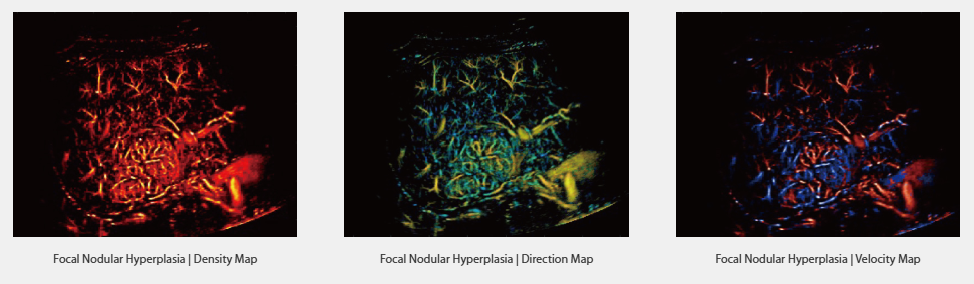

Инновационные клинические исследования

Оснащенная широким спектром передовых технологий визуализации, система Resona A20 дает возможность врачам проводить достоверные клинические исследования. Технология сверхразрешающего контрастного ультразвука (Super Resolution CEUS, SR CEUS) позволяет визуализировать детали кровоснабжения органов и мягких тканей, что помогает врачам выявлять ранние изменения микрогемодинамики в патологических очагах.

Super Resolution CEUS

Благодаря платформе AIT, система Resona A20 предлагает комплексное решение для визуализации в сверхвысоком разрешении — возможность, которой раньше не было. Технология SR CEUS (сверхразрешающий контрастный ультразвук) обеспечивает визуализацию мелких сосудов и их кровотока с детализацией на уровне микронов, что позволяет изучать микроциркуляцию в патологических очагах, включая опухоли. Это особенно полезно для оценки перфузии тканей и диагностики онкологических заболеваний на ранних стадиях.

-

Разрешение на уровне микронов

-

Возможности обнаружения микрокапилляров

-

Инструменты количественного анализа

-

Фокальная узловая гиперплазия

-

Фокальная узловая гиперплазия

-

Фокальная узловая гиперплазия